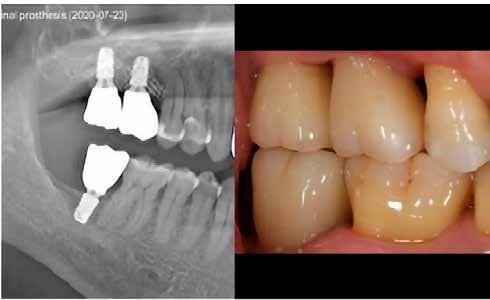

8. a–b. ábra: Végső röntgenfelvétel az implantátum helyzetéről (a) és a szájon belüli végső szituáció az 1. esetről (b).

9. a–b. ábra: Végső röntgenfelvétel az implantátum helyzetéről (a) és a szájon belüli végső szituáció a 2. esetről (b).

tottuk (az okklúziós koncepciók alapján az implantációs pótlások nem voltak vezető fogak, és csak könnyű érintkezéseket alakítottunk ki, amelyeket artikulációs papírral ellenőriztünk). A páciensek instrukciókat kaptak a megfelelő szájhigiénére vonatkozóan, összpontosítva a fogköz kefékkel történő tisztítására. Végső kontroll röntgenfelvétel készült. A PEEK felépítmény nem radioopák, így az implantátum és a korona közötti távolság könnyen meghatározható a röntgenfelvételen: a felépítmény megfelelően illeszkedik az implantátumban, ha az implantátum válla és a korona alsó széle közötti rés 0,55 mm a röntgenfelvételen (8–11. ábra)